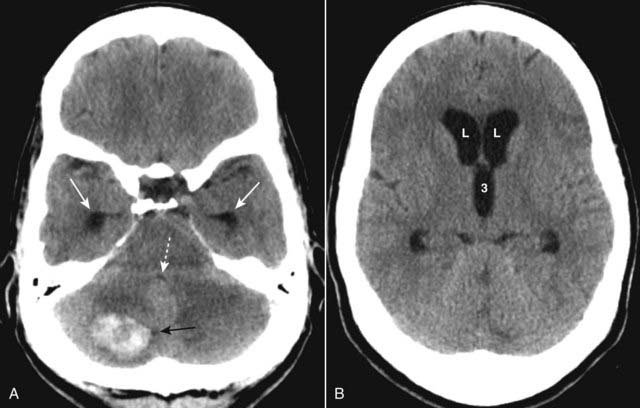

imageEither of these mechanisms can produce a cerebral contusion. Contusions are hemorrhages with associated edema usually found in the inferior frontal lobes and temporal lobes on or near the surface of the brain (Fig. 25-10).

image CT findings of intracerebral hemorrhage change over time and may not be immediately evident on the initial scan. MRI typically demonstrates the lesions from the time of injury, but may not be available on an emergency basis.

image Recognizing traumatic intracerebral hemorrhage on CT

Cerebral contusions may appear as multiple, small, well-demarcated areas of high attenuation within the brain parenchyma (see Fig. 25-10A).

They may be surrounded by a hypodense rim from edema (see Fig. 25-10B).

Intraventricular blood may be present (Fig. 25-11).

Mass effect is common. The mass effect may produce compression of the ventricles and shift of the 3rd ventricle and septum pellucidum to the opposite side. Such displacement can produce severe brain or vascular damage.

These displacements are called herniations. Patients with sufficient mass effect are at risk for transtentorial and subfalcine brain herniation and death (see Fig. 25-10B).

The types of brain herniation are described in Table 25-5 (Fig. 25-12).

Figure 25-10 Cerebral contusions.

A, Cerebral contusions are usually the result of trauma and can manifest by multiple areas of high attenuation hemorrhage (solid white arrows) within the brain parenchyma on CT. B, Contusions (solid black arrow) are frequently surrounded by a rim of hypoattenuation from edema (dotted black arrow), and mass effect is common, as is demonstrated here by amputation of the ipsilateral basilar cisterns (dotted white arrow), midline displacement (solid white arrow) representing subfalcine herniation, and dilatation of the contralateral temporal horn (white circle). A portion of the left side of the skull has been surgically removed, and there is a large scalp hematoma present (dashed white arrow).

image

Figure 25-11 Intraventricular hemorrhage.

Intraventricular hemorrhage (solid white arrows) is common in premature infants but less common in adults. It usually results from break-through bleeding from a brain contusion or subarachnoid hemorrhage and requires a considerable amount of force to produce. Therefore, it is typically associated with severe brain damage and has a poor prognosis.